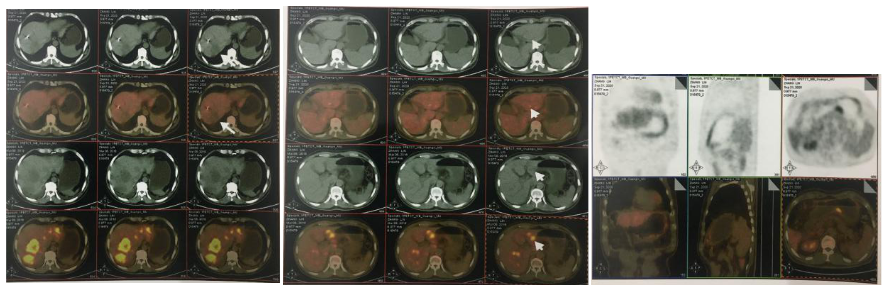

2018-03-08 PET/CT示:胃癌(?)并全身多发淋巴结转移、肝脏多发转移、双肺上叶多发转移;

2018-11-19 PET/CT

胃壁代谢稍增高但未见明确的肿物,肝内低代谢结节考虑转移瘤治疗后活性减低,纵膈及右肺门两个淋巴结代谢增高,考虑转移瘤活性尚存、左侧颞骨局部骨质破坏并代谢增高,考虑转移瘤。

经科内讨论,建议患者继续原方案SOX+赫赛汀化疗,左侧颞顶交界区骨质破坏局部射波刀治疗。

2018-12-11行肝内病灶射波刀立体定向放射治疗,具体为:肝转移瘤病灶(4个)40Gy/3f;